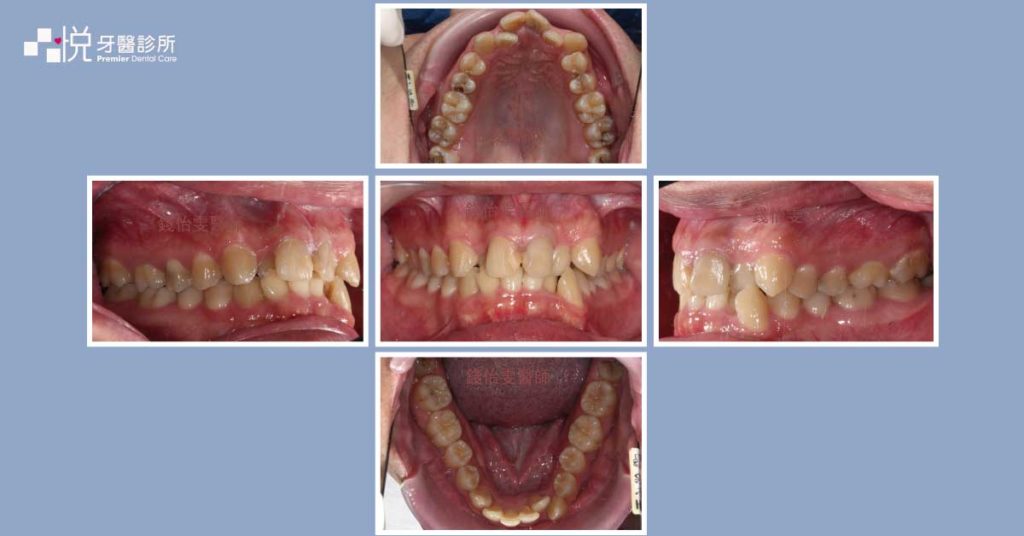

牙齒矯正前的資料收集包括拍攝口內外照片、全口 X 光片、正側顱 X 光片(或其他需要的 X 光片)、製作全口模型等等,矯正醫師有充足的資訊可以去做分析每位患者口內外的情況,診斷出問題所在,並且擬定專屬且適合的矯正治療計畫,可以在下一階段的矯正諮詢有更充沛的說明喔!